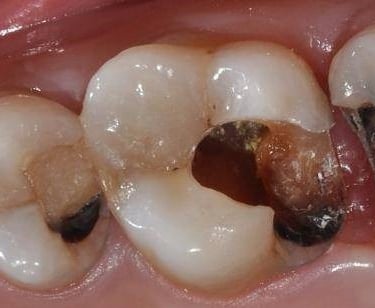

Caries Radicular

La caries radicular es la descomposición del cemento y la dentina en la raíz del diente, común en personas mayores con recesión gingival.

Los pacientes pueden experimentar sensibilidad y dolor en la raíz expuesta.

El tratamiento incluye la eliminación de la caries y la restauración de la raíz. La prevención incluye una buena higiene oral y el uso de flúor.